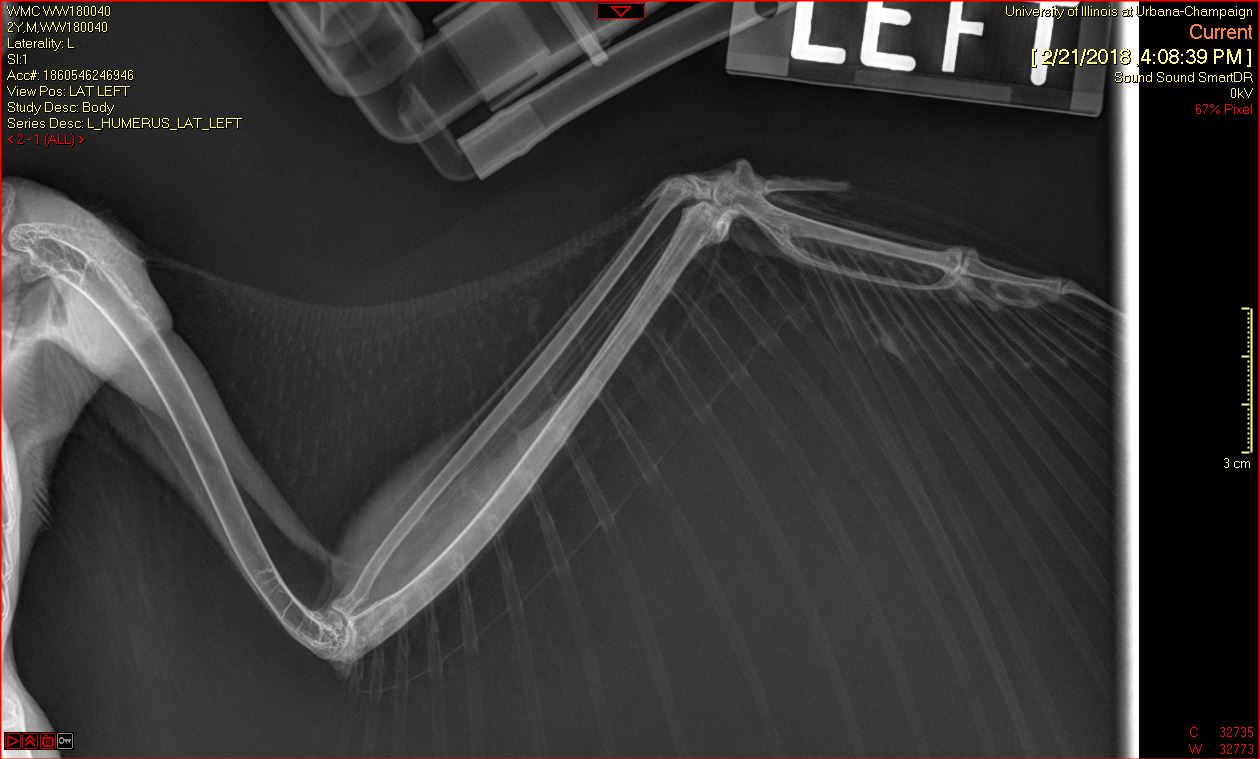

A Barred Owl was transferred to the Wildlife Medical Clinic from a nearby veterinary clinic on February 20th after being hit by a car on February 18th. In their initial exam, the team noticed an open fracture on the middle of the right humerus of the wing. Radiographs (x-rays) showed that the wing had been rotated a complete 360 degrees!

Once the wing was rotated back into normal position, the team had to wait to assess whether the portion distal to the rotation (closer to the wing tip) still had healthy blood supply. Once this was ensured, they determined the owl was a good candidate for surgery to repair the humeral fracture.